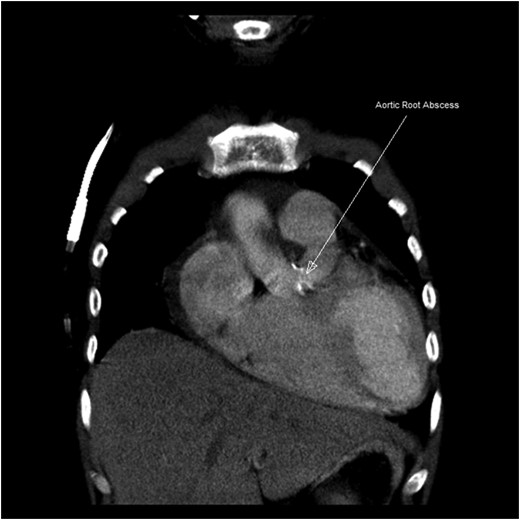

We report an end-stage renal disease (ESRD) patient on regular haemodialysis awaiting renal transplant having native aortic valve endocarditis due to Acinetobacter baumannii complicated with aortic root abscess and severe mitral valve regurgitation with NYHA class IV symptoms. He underwent emergency aortic root abscess debridement, reconstruction with autologous pericardial patch and bioprosthetic aortic valve replacement along with mitral valve repair. This emergency intervention in active infective endocarditis due to A. baumannii and associated ESRD is very rare. We could not trace any case report for such combination of clinical scenario in the literature.

The literature is limited on outcomes of valvular replacement surgery in dialysis-dependent end-stage renal disease (ESRD) patients with active bacterial endocarditis [1]. Aortic root abscess is a complication of aortic valve infective endocarditis having high morbidity and mortality. Infective endocarditis due to Acinetobacter baumannii is very rare. Early diagnosis and prompt surgical intervention is must to save the life of a patient. We operated a 39-year-old patient having severe aortic regurgitation, severe mitral regurgitation, active bacterial endocarditis and aortic root abscess due to A. baumannii with dialysis-dependent ESRD.

Endocarditis affecting the aortic valve leading to abscess formation is particularly challenging to treat and requires aggressive diagnostic and therapeutic approaches because of severe complications such as conduction block, destruction of surrounding tissue, fistula to other cardiac chambers, aortic pseudoaneurysm formation and extrinsic compression of coronary arteries [5]. The most important aspect in the surgical treatment of these patients is radical debridement of all infected tissues. Reconstruction with pericardial patch and valve replacement with either aortic prosthetic valve or homograft is done. In our case, bioprosthetic valves were used because homografts were not available in emergent situations, and the cost of a homograft is also too expensive to procure it on emergency basis. Due to the limitation of related articles of similar clinical scenario of aortic root abscess due to A. baumannii in dialysis-dependent patient along with intervention for two cardiac valves, there was no possibility of further survey and comparison.